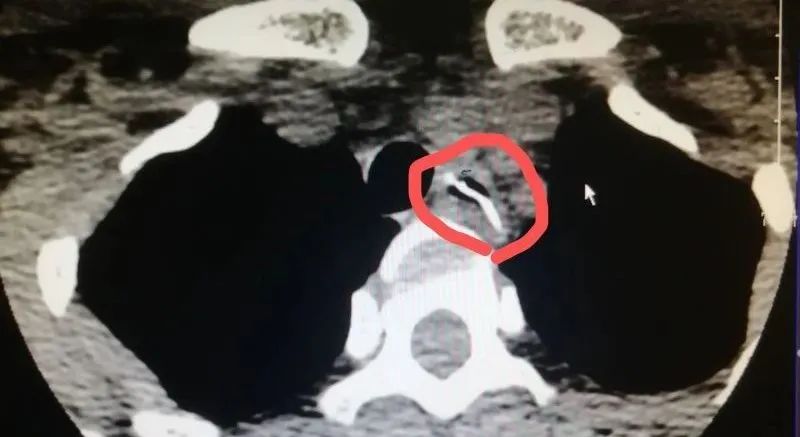

原以为最多只是做个胃镜的家人,被检查结果震惊了!经胸部CT检查发现,有一块约3×2cm的鱼骨头卡在食管内,就紧贴胸主动脉弓,病情十分紧急!

鱼骨位于在食管与主动脉弓水平处,食管周围组织水肿明显,食管与主动脉间隙十分不清晰,可能已损伤主动脉壁。如果消化内科在内镜下盲取,可能会造成主动脉大出血。最终专家组制定了手术方案,由心胸外科及血管外科共同上台,开胸手术取出鱼骨。